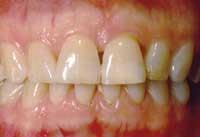

Before and after photos of the same patient.

Functional stability, health, and youthful appearance were achieved with the single implant.

The surgeon who placed the implant is Dr. Leonard Garfinkel of Aventura, Fla.